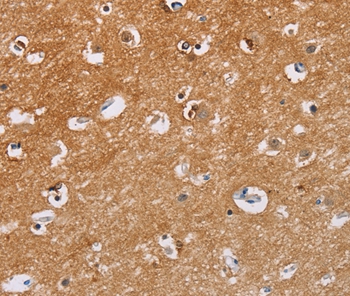

图片:

Immunohistochemical analysis of paraffin-embedded Human brain tissue using #35658 at dilution 1/40.